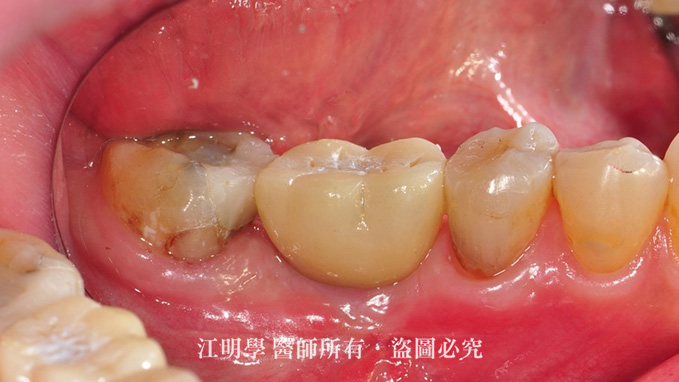

治療前:大臼齒缺牙